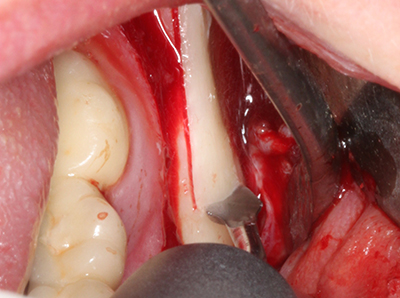

Fig. 3: Basal separation of the block is easier with specially angled attachments.

Fig. 13: Adequate irrigation with the 4-mm residual bone width is essential for this 52-year-old patient during the bone splitting.